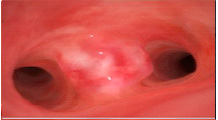

逆流性食道炎、胃潰瘍

食道のヘルニア、びらん性胃炎、十二指腸潰瘍

バレット食道、胃憩室、びらん性胃炎

噴門機能障害、胃の腫瘤、肥厚性十二指腸炎

食道静脈瘤、十二指腸ポリープ、胃萎縮

食道憩室、消化管間質腫瘍

食道がん、十二指腸ポリープ

胃粘膜肥大を伴うびらん性胃炎

浸潤性胃がん

外方増殖性の胃腫瘍